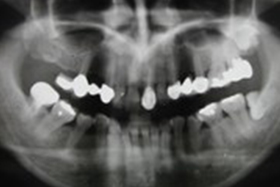

假牙拆除前的X光片,可看出假牙已不密合